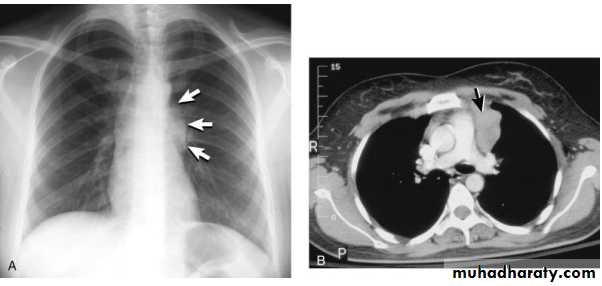

On a posteroanterior chest x-ray (A), the left hemithorax is very dark or lucent because the left lung has collapsed completely (white arrows).The tension pneumothorax can be identified because the mediastinal contents, including the heart, are shifted toward the right, and the left hemidiaphragm is flattened and depressed. A computed tomography scan done on a different patient with a tension pneumothorax (B) shows a completely collapsed right lung (arrows) and shift of the mediastinal contents to the left.